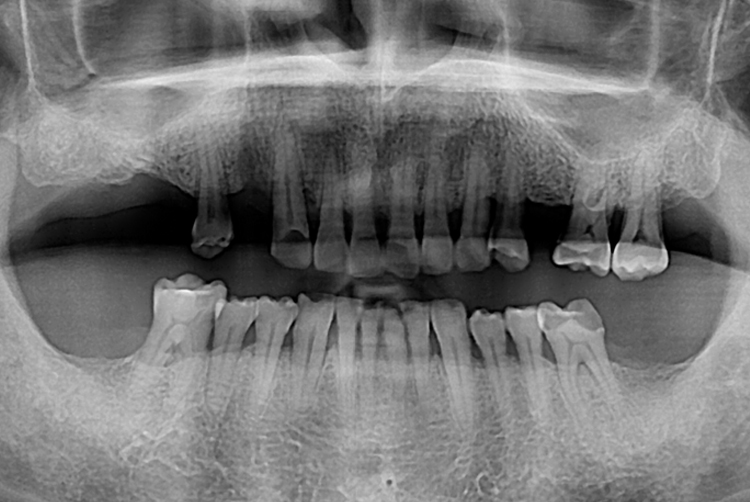

[임플란트] 임플란트

치료전 : 2019-03-07